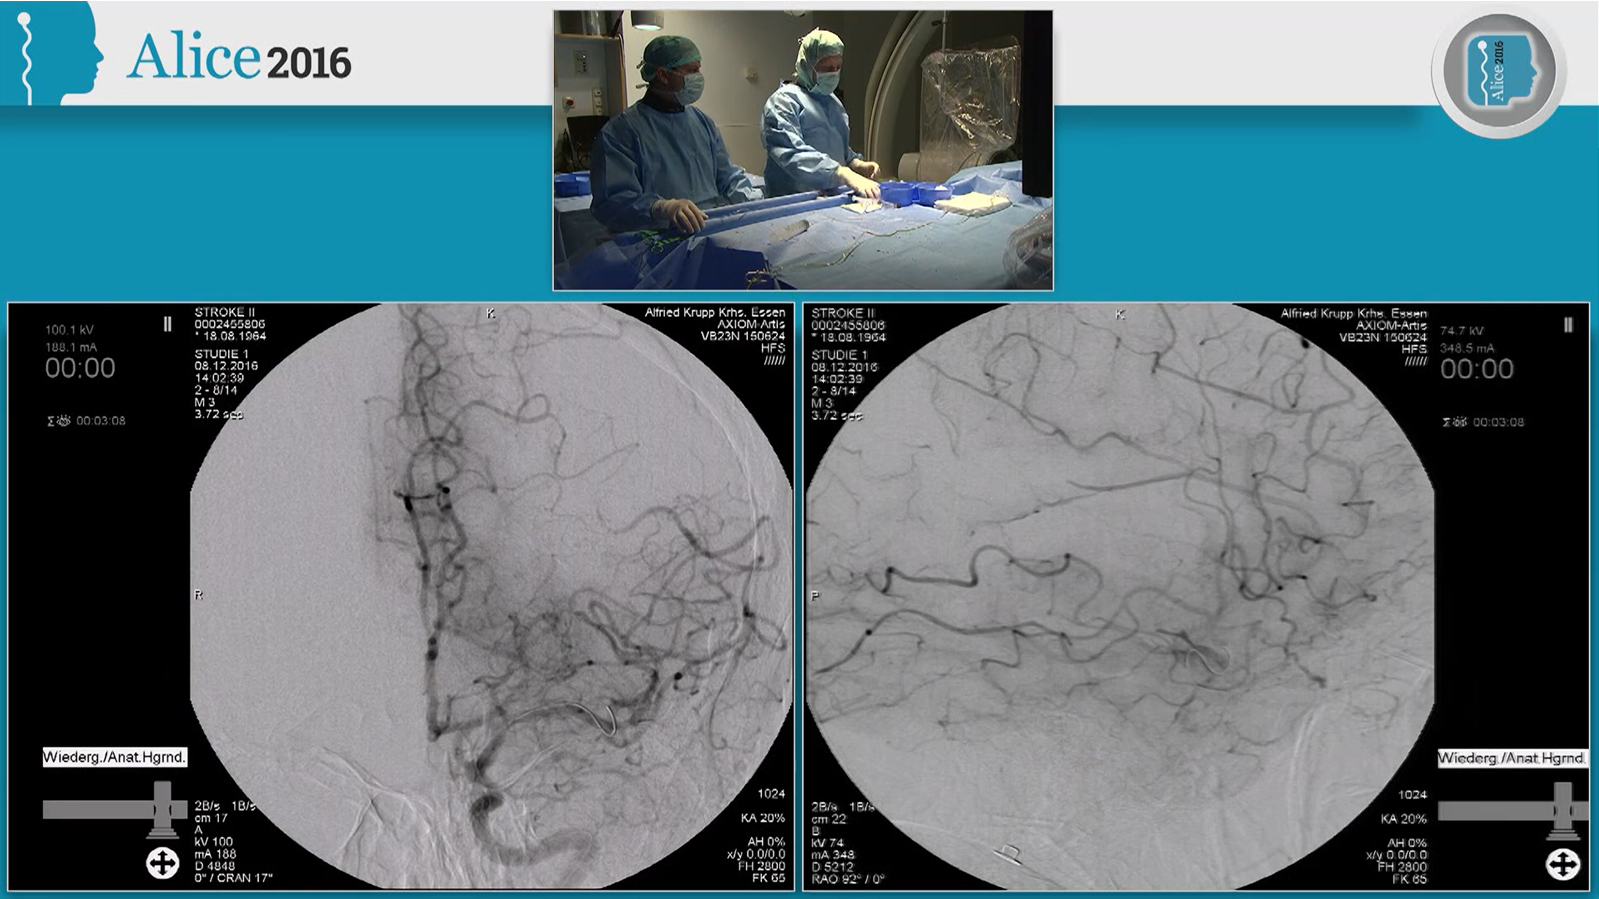

Tandem occlusion thrombectomy with Solitaire and Stenting with Wallstent